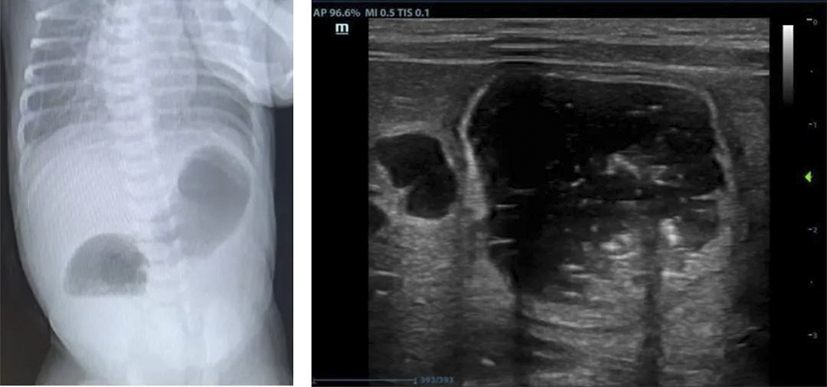

十二指腸閉鎖是一種先天性消化道畸形,發(fā)病率約1/50000至1/10000,占所有腸閉鎖的50%以上,約30%合并唐氏綜合征,也可能伴隨其他先天異常(如心臟畸形、腸旋轉(zhuǎn)不良等)。產(chǎn)前主要表現(xiàn)為母體羊水過多,超聲可見胃和十二指腸近端擴(kuò)張(“雙泡征”)。出生后表現(xiàn)為24-48小時(shí)內(nèi)嘔吐、上腹部膨隆、排便減少或無胎糞排出等。通過產(chǎn)前超聲、出生后X線檢查可以明確診斷,手術(shù)是唯一的治療方法。微創(chuàng)腹腔鏡手術(shù)具有創(chuàng)傷小、出血少、術(shù)后恢復(fù)快、縮短住院時(shí)間等優(yōu)勢(shì),目前已廣泛應(yīng)用于十二指腸閉鎖的治療。